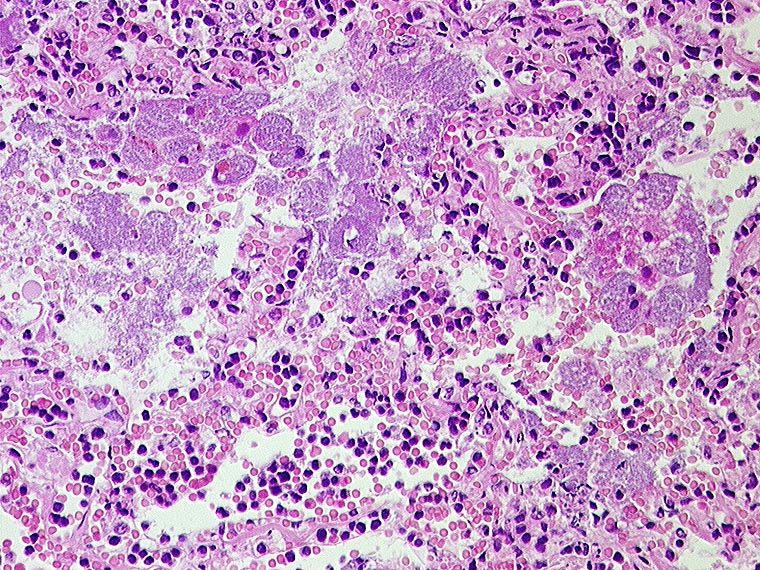

AP/ Areaktive Pneumonie

Areaktive Pneumonie

Entzündung infektiös

Lunge

Morphologie